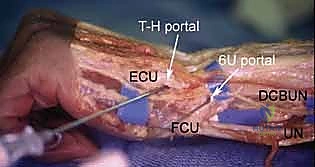

3. The Triquetrohamate Portal (T-H)

- Location: Enters the midcarpal joint at the level of the triquetrohamate joint, ulnar to the ECU tendon. Its entry site is both ulnar and distal to the midcarpal ulnar portal.

- Anatomy: Directly accesses the articulation between the triquetrum and hamate.

- Neurovascular Risks: Branches of the dorsal cutaneous branch of the ulnar nerve are most at risk here.

- Function: A special-use portal for specific pathology localized to the triquetrohamate joint.

2. The Volar Ulnar Portal (VU)

- Location: Located underneath the ulnar border of the flexor tendons (specifically the flexor carpi ulnaris, FCU, and flexor digitorum sublimis, FDS) at the level of the proximal wrist crease.

- Anatomy: The interval between the FCU and FDS tendons.

- Neurovascular Risks: HIGH. The ulnar nerve and ulnar artery are immediately radial to the FCU tendon. The palmar cutaneous branch of the ulnar nerve is also vulnerable. Extreme caution and meticulous blunt dissection are mandatory.

- Function: Indicated for visualizing and débriding palmar tears of the lunotriquetral ligament (LTIL). It aids in the repair or débridement of dorsally located TFCC tears, especially when triangulation from dorsal portals is difficult. It also assesses the dorsal radioulnar ligament, the ECU subsheath, and the radial TFCC attachment.

Most of the complications related to use of the dorsal portals are related to injury to the sensory branches of the superficial radial nerve and the dorsal cutaneous branch of the ulnar nerve.

There is no true internervous plane when using the volar ulnar portal; hence, sensory branches of the palmar cutaneous branches of the ulnar nerve or nerve of Henle are always at risk. Thus, proper wound spread technique is paramount.

The ulnar neurovascular bundle is also potentially at risk with overzealous retraction or poor portal placement.